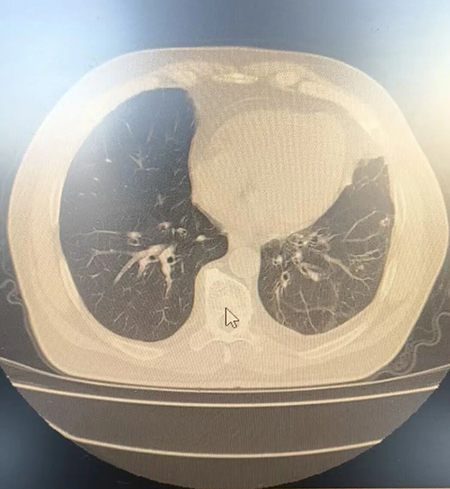

肺部CT检查显示的支气管扩张症